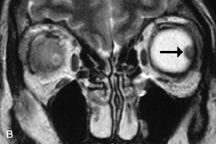

Application of a 90° RF pulse brings the excited nuclei into phase so that the net vector of their magnetic moments is directed perpendicular to the static magnetic field. Shortly thereafter, the magnetic moments of the nuclei spread out and point in different directions, leading to a loss of phase coherence and a resultant decay in signal intensity amplitude. The T2, or spin-spin relaxation time, is the rate of decrease in the signal of these excited nuclei as a result of the interaction and transfer of energy to unexcited adjacent nuclei. T2 ranges from a few milliseconds to a few hundred milliseconds and, for a given tissue, is always less than the Tl relaxation time. T2-weighted orbital images are easily recognized by a high-intensity signal from the vitreous (Fig. 9).5,8,16